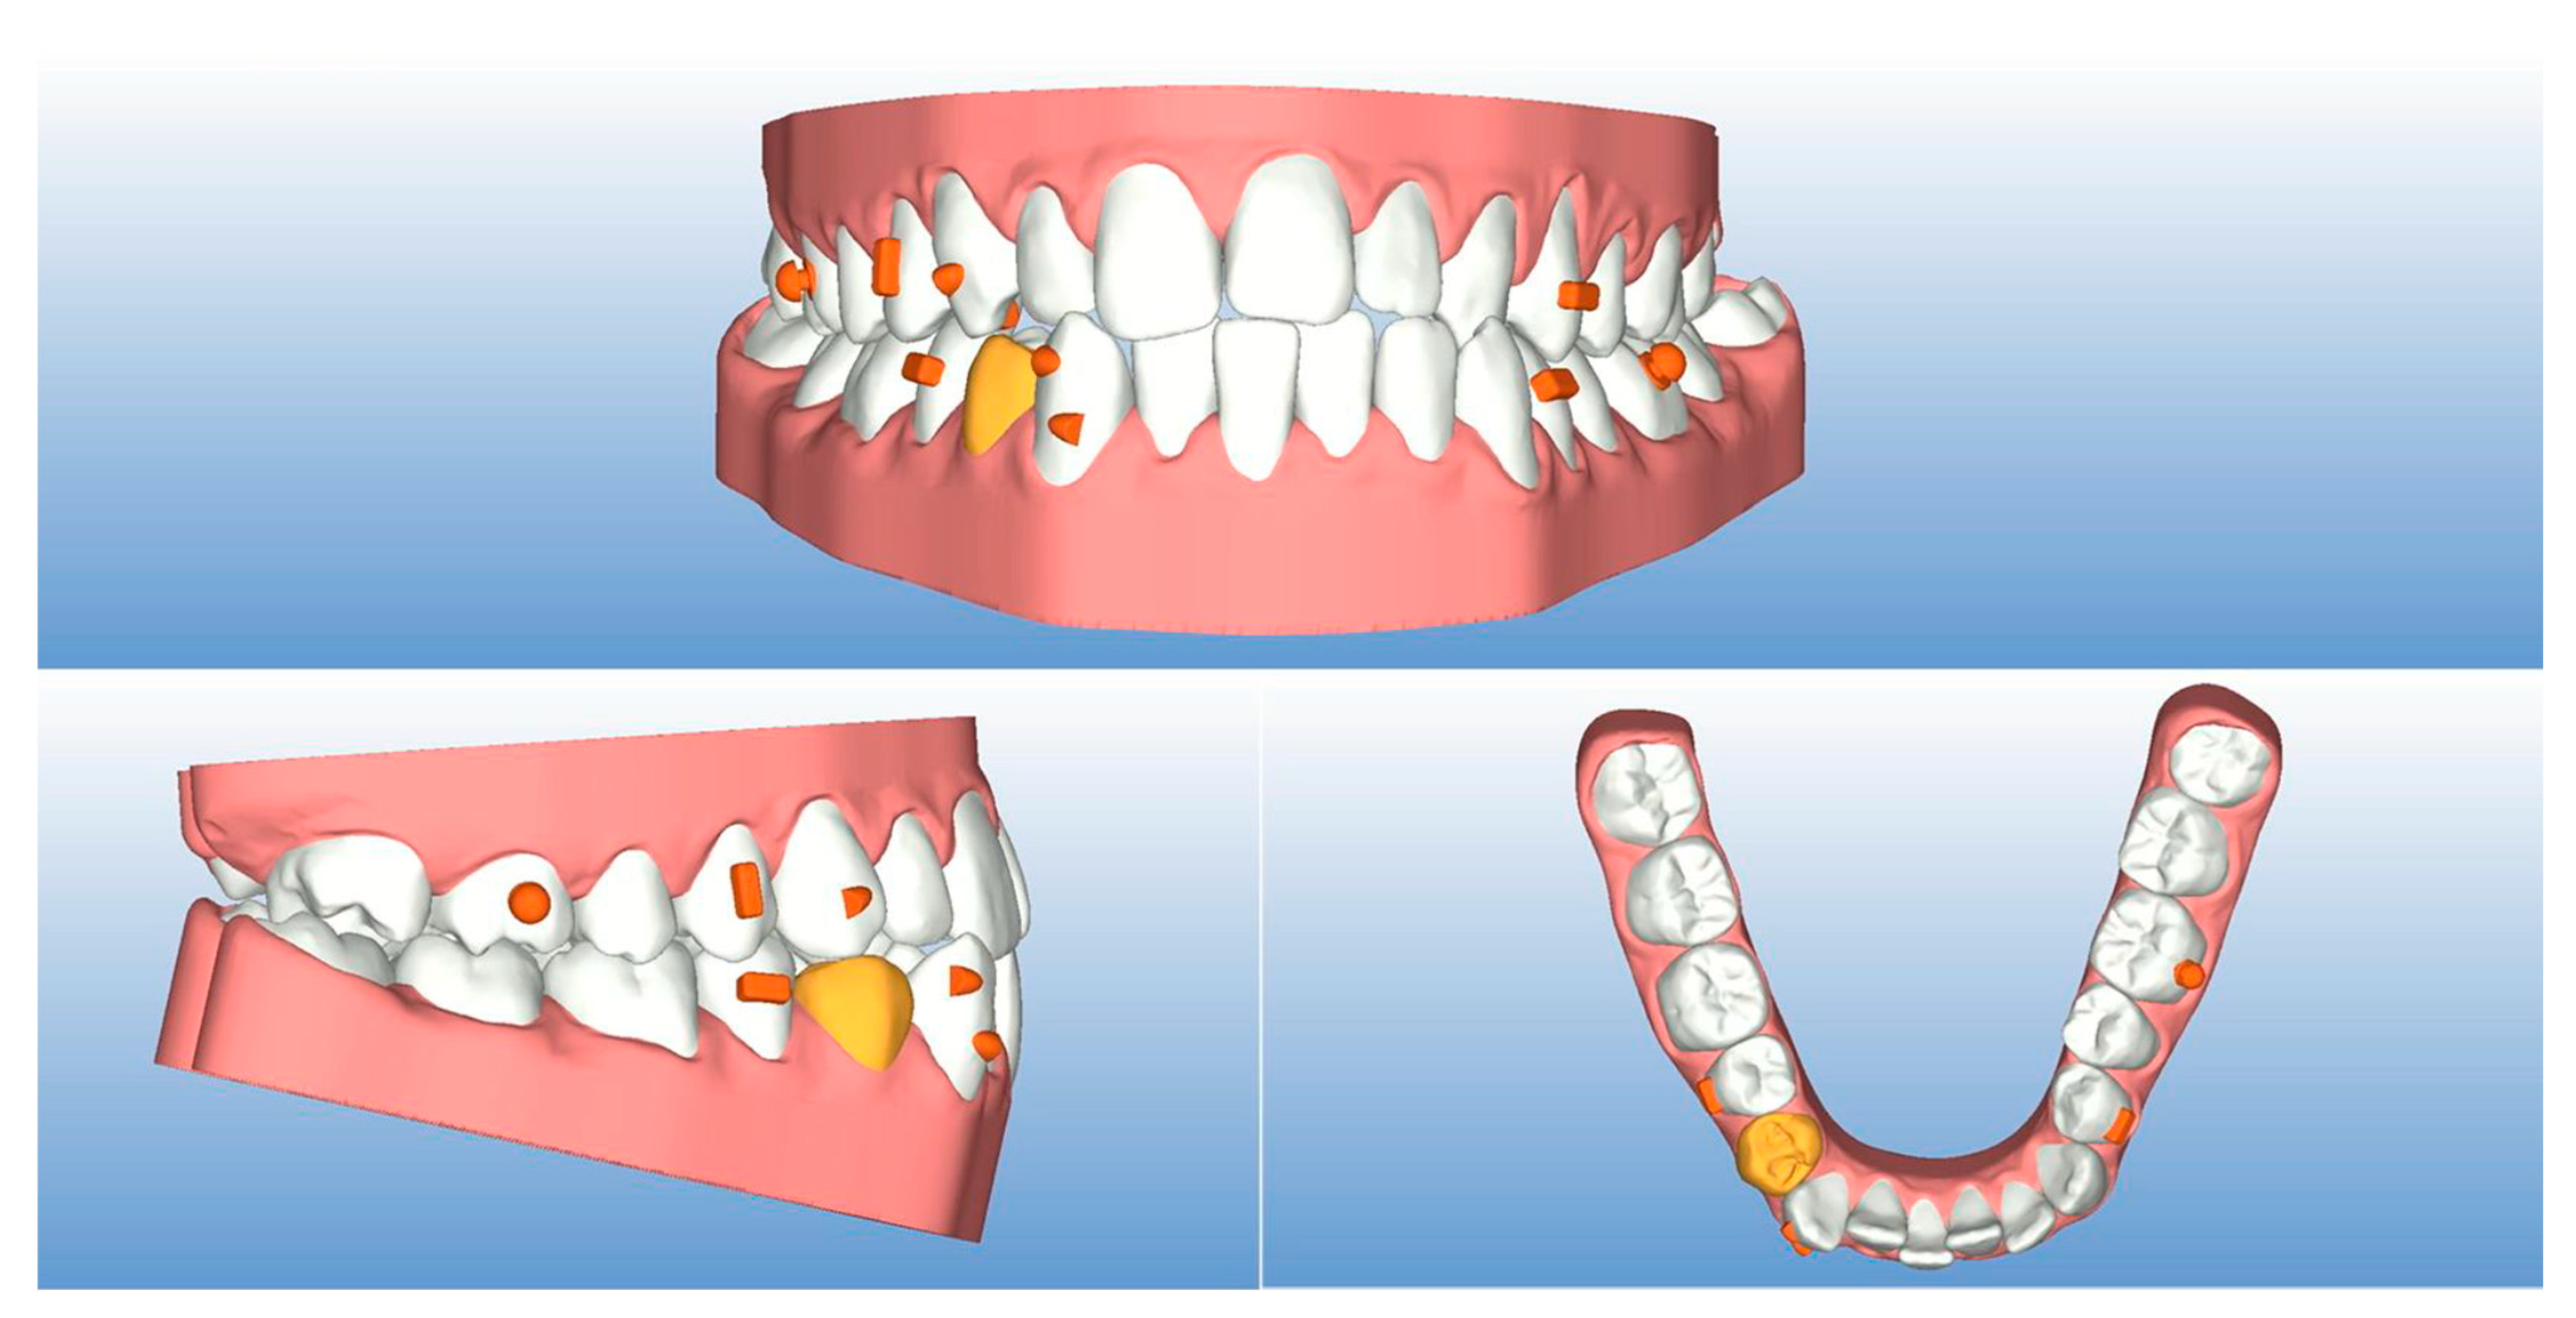

| Measurements | Initial | Final | Norm |

|---|---|---|---|

| SNA (°) | 86.7 | 87.5 | 82.0 ± 3.5 |

| SNB (°) | 84.1 | 84.9 | 80.0 ± 3.5 |

| ANB (°) | 2.6 | 2.6 | 2.0 ± 2.5 |

| SN^ANS-PNS (°) | 7.2 | 6.3 | 8.0 ± 3.0 |

| SN^GoGn (°) | 37.7 | 37.7 | 33.0 ± 2.5 |

| ANS/PNS^Go-Gn (°) | 33.3 | 33.3 | 25.0 ± 6.0 |

| U1^ANS-PNS (°) | 113.2 | 111.8 | 110.0 ± 6.0 |

| L1^GoGn (°) | 85.1 | 80.4 | 90.0 ± 6.0 |

| L1 Protrusion (L1-APo) (mm) | 1.6 | 1.3 | 1.0 ± 2.5 |

| Overjet (mm) | 2.6 | 2.4 | 2.5 ± 2.5 |

| Overbite (mm) | 0.6 | 1.5 | 3.0 ± 2.5 |

| U1^L1 (°) | 131.1 | 136.4 | 135.0 ± 6.0 |

| Co-Go-Me (°) | 123.9 | 124.8 | 125.0 |

| Lower lip to Ricketts E-line (mm) | −4.8 | −5.6 | 0.0 ± 2.0 |